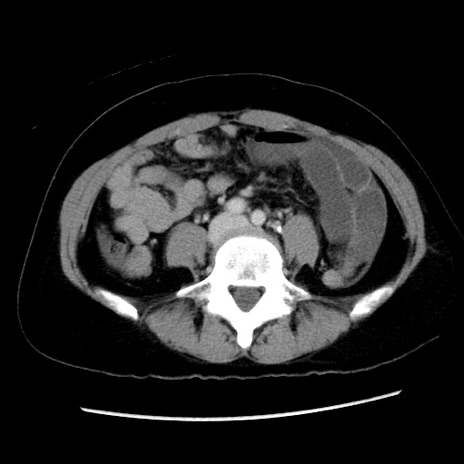

冠状断像